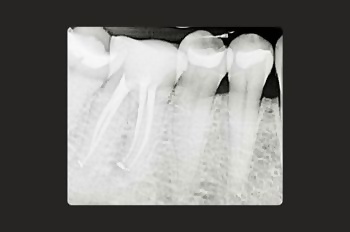

Root canal treatment is a gentle procedure that feels very similar to getting a filling when performed by a skilled dentist with training in minimally invasive practices.

Our patients are often pleasantly surprised at the ease and comfort of the experience.

We understand that some patients may be nervous and require support in relaxing before and during the procedure.